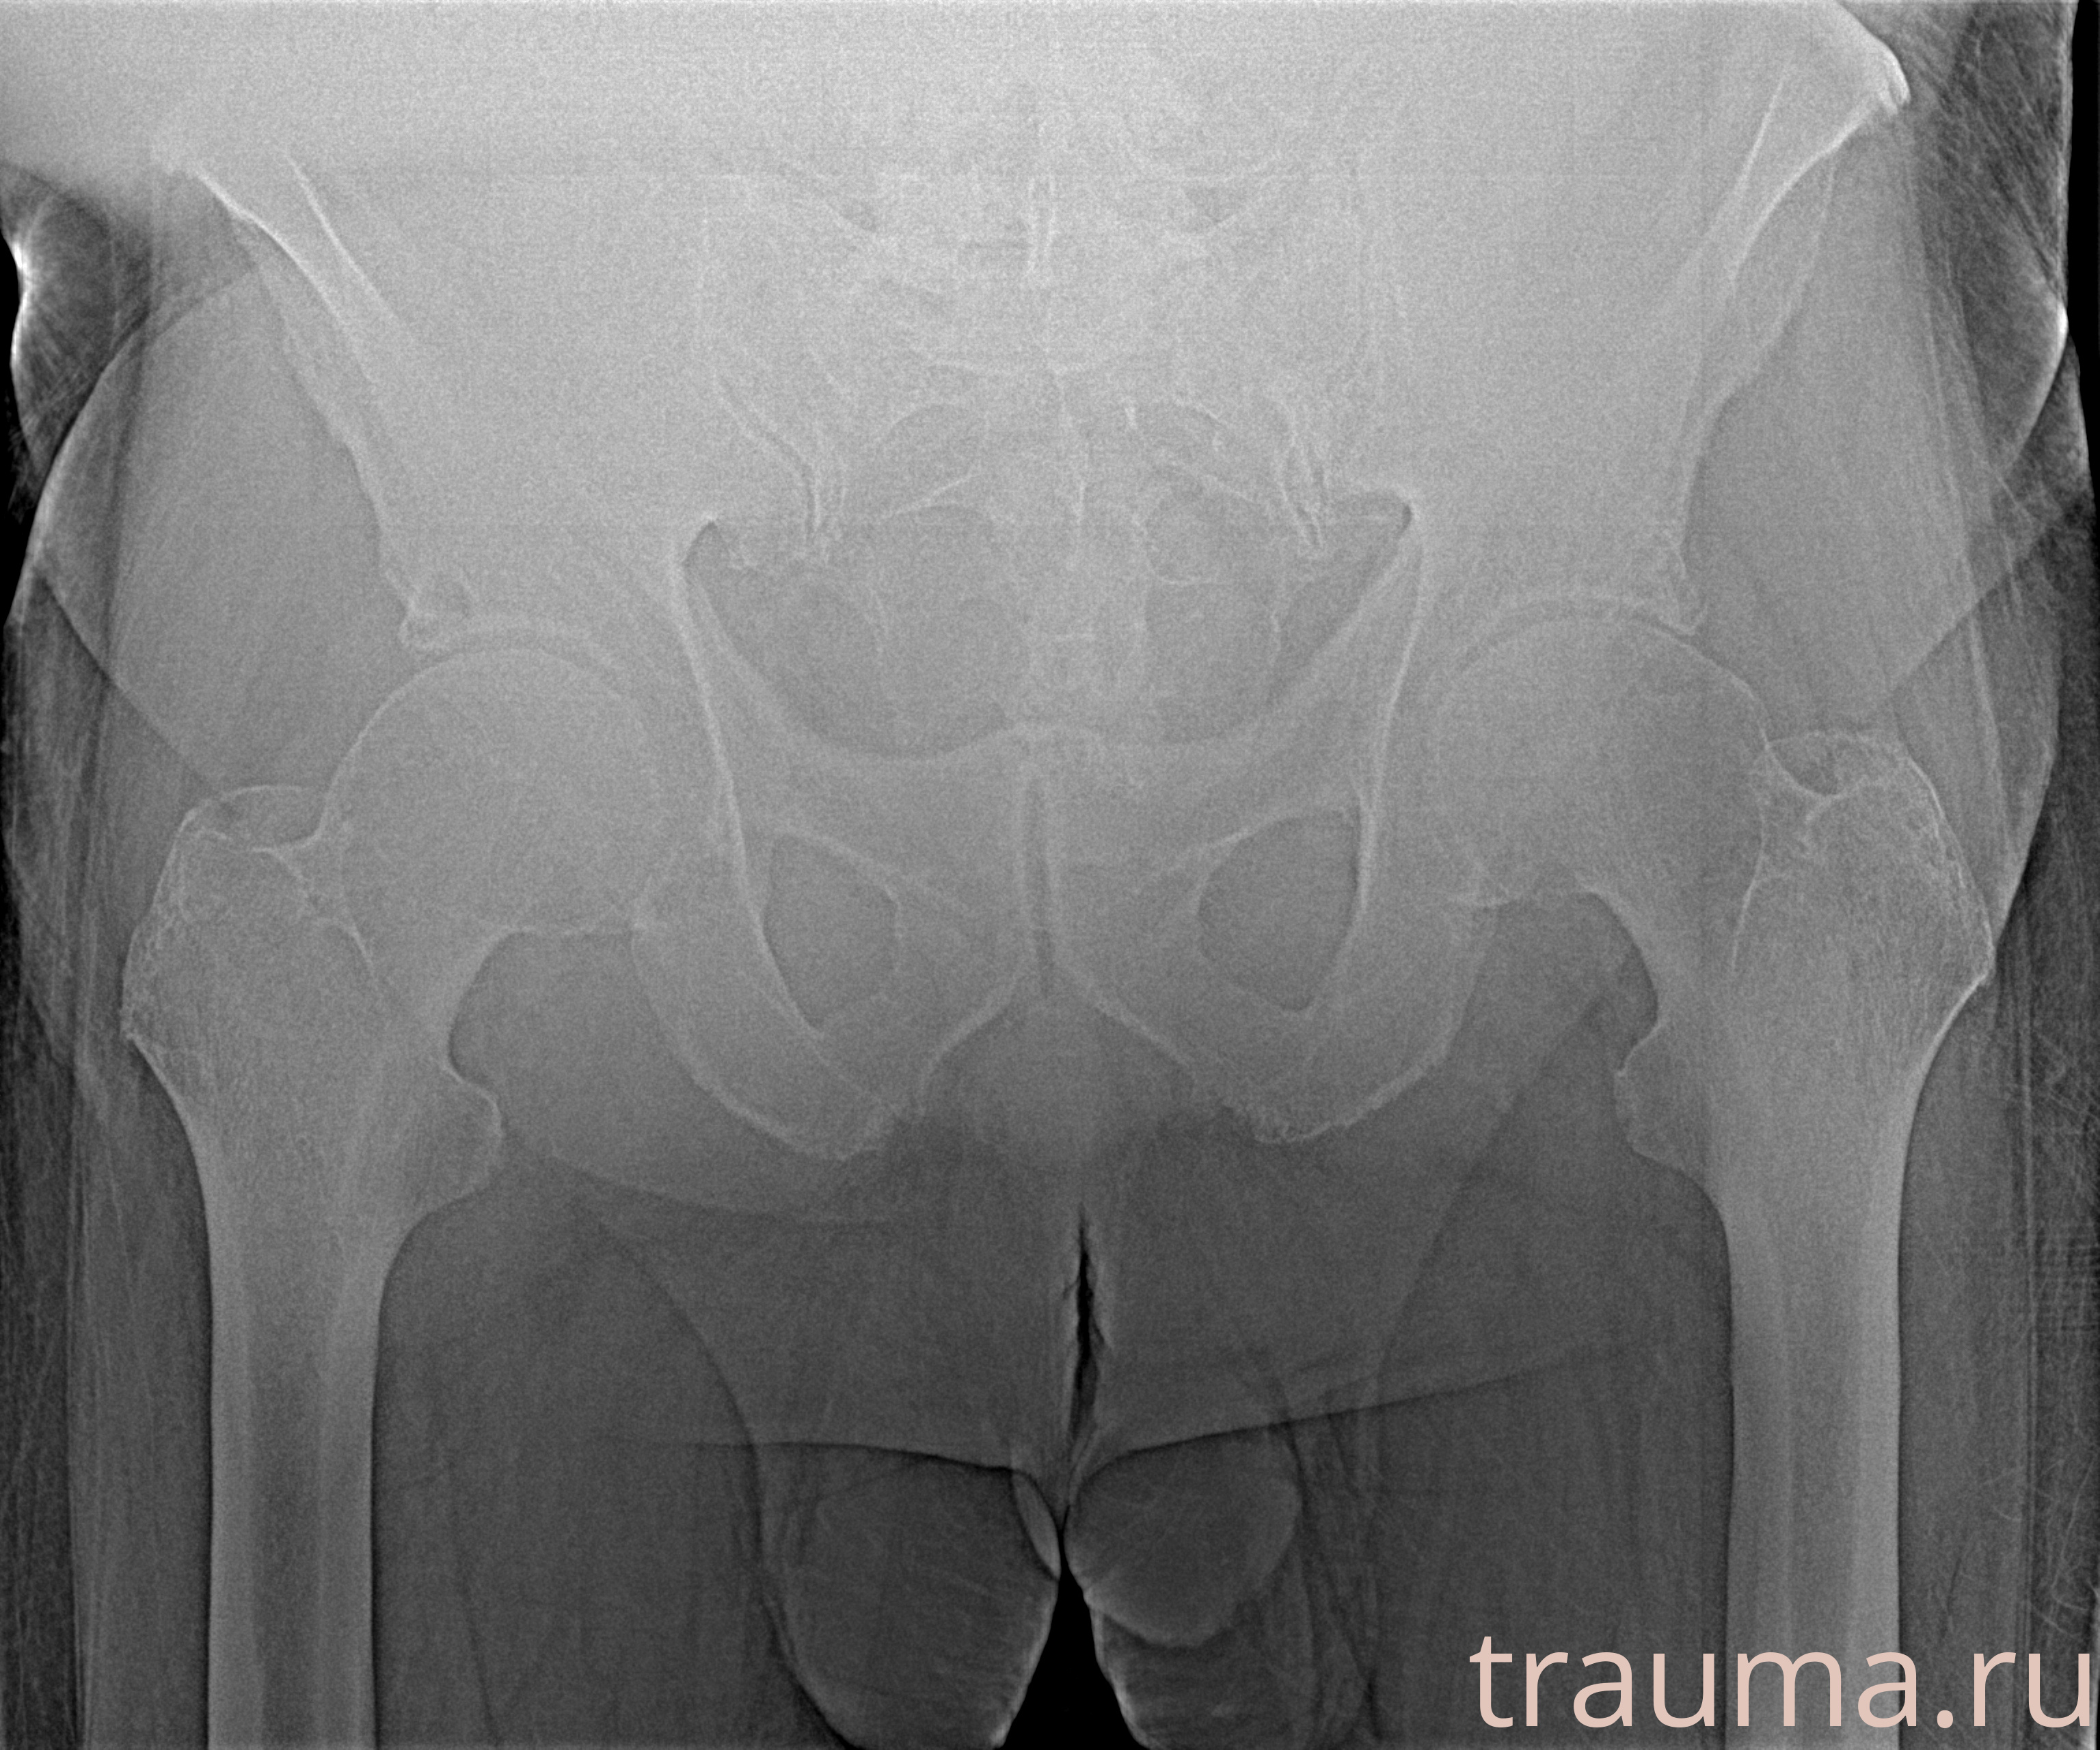

Рентген на дому: по вашему адресу приезжает врач-рентгенолог, травматолог-ортопед с мобильным рентгеновским аппаратом, проводит диагностику травмы или заболевания, делает необходимые рентгенограммы, дает рекомендации по дальнейшему лечению. Получить качественные снимки в домашних условиях возможно благодаря уникальной методике, разработанной МосРентген Центром для института  Склифосовского